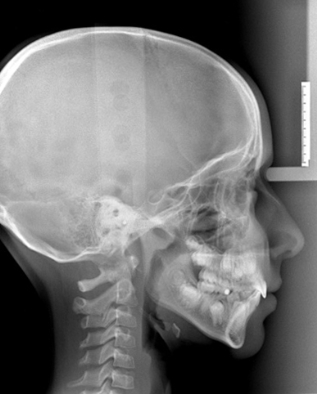

Teleradiografia digitale